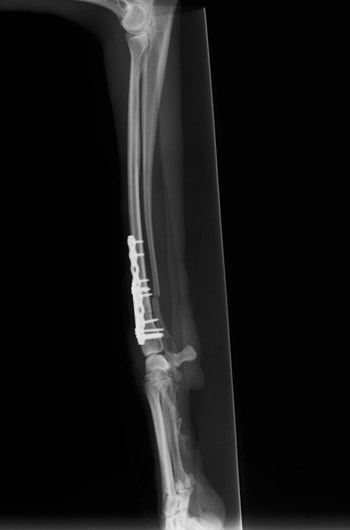

症例3:キルシュナーワイヤーのピンニングによる整復

ペルシャ猫 11ヶ月齢 雄

他院にて左大腿骨遠位の成長板骨折(salter-harrisⅠ型)が認められており、治療相談を目的として来院。当院にて、キルシュナーワイヤーを用いたピンニングにより骨折部位の整復を行いました。術後の経過は良好で、現在も経過観察中です。

術前レントゲン

術後レントゲン